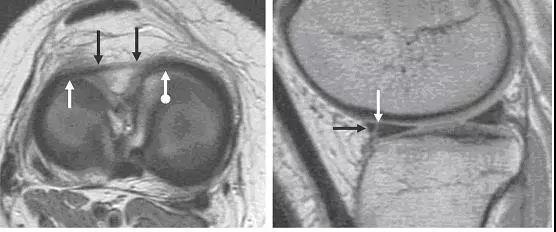

图 11 内侧半月板桶柄状撕裂——双后交叉韧带征

左图:经髁间切迹的矢状面,可见剥离开的低信号半月板块(白色箭头)平行于正常的后交叉韧带(黑色箭头)。右图:冠状面可见剥离的半月板块(白色直箭头),在正常的后交叉韧带(黑色箭头)下方。残留的半月板外缘(白色圆箭头)形态异常且比正常(对侧)的小。